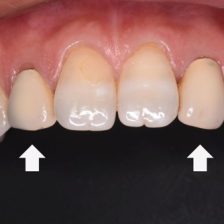

むし歯治療

審美歯科

保険適用の白い歯

症例集